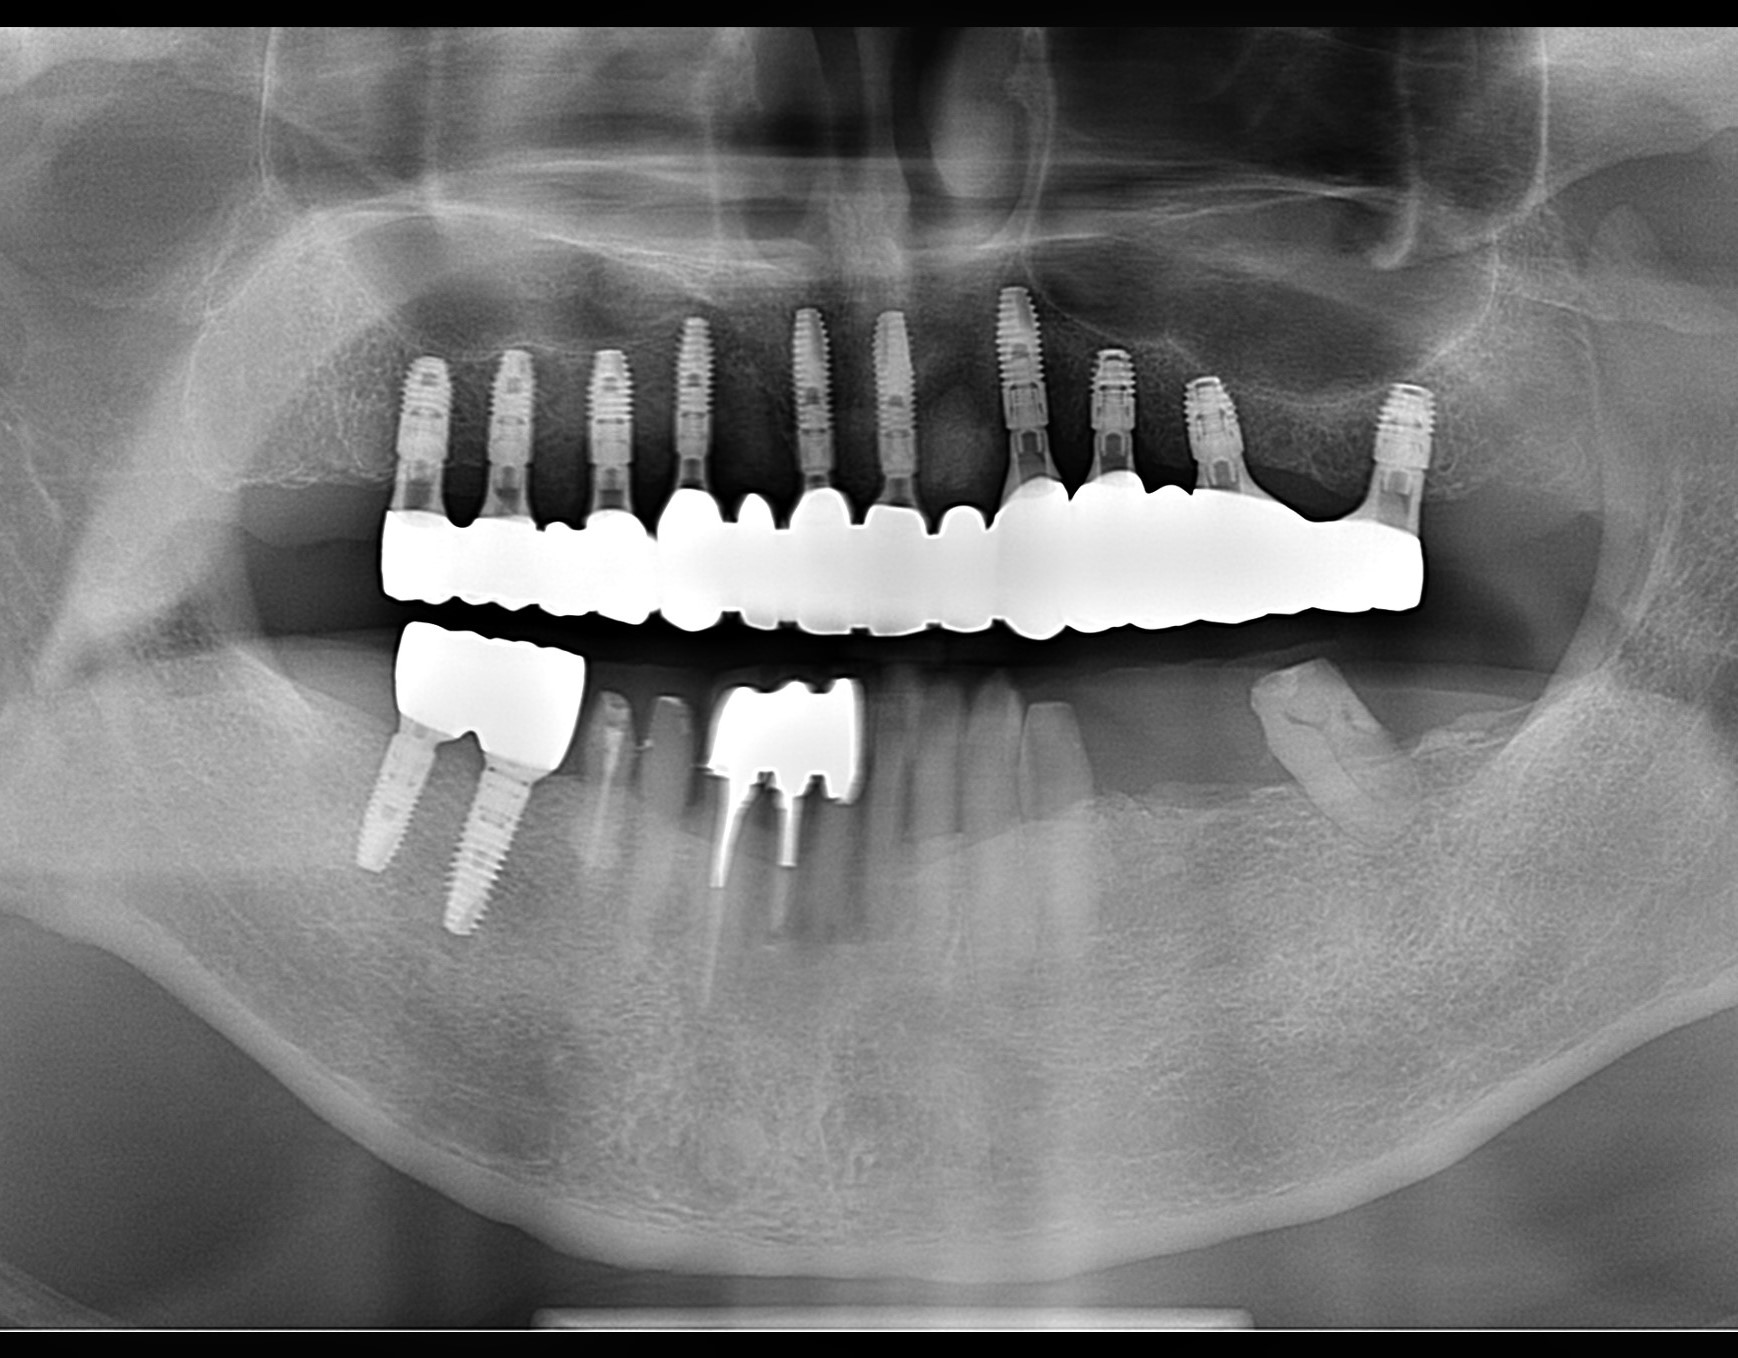

この患者さんは、総入れ歯ではなく、固定式のボーンアンカードブリッジを希望され、昨年末に1回の手術で10本のインプラントを埋入しました。

ただ、そのままボーンアンカードブリッジを装着すると頬粘膜を噛んでしまいます。頬粘膜にある脂肪体をある程度切除して、縮小する必要がありました。

そこで静脈内鎮静法を行って局所麻酔で頬脂肪体を切除し、吸収性の糸を使って縫合しました。

P7.pano